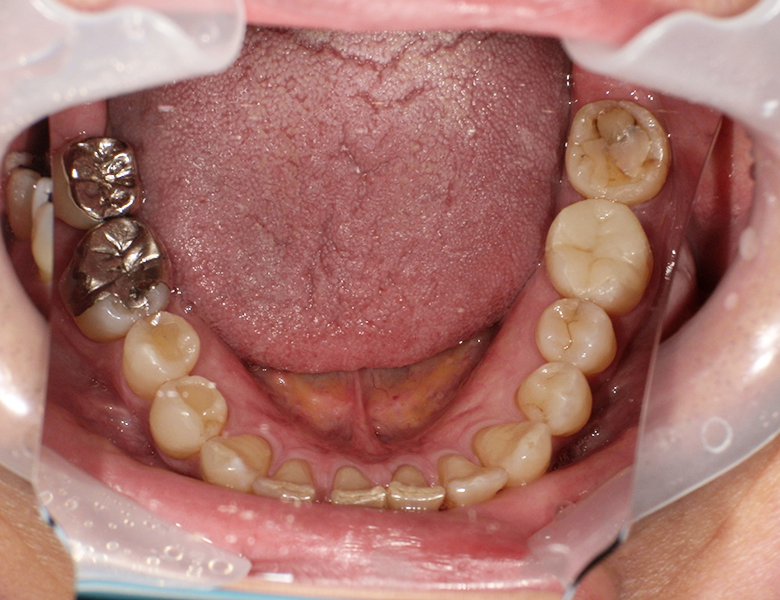

治療後 ![]() |

劣化した金属修復物を除去し、う蝕部分を適切に除去したうえで、メタルフリー修復としてジルコニアインレーによる治療をご提案しました。強度と適合性、自然な色調を重視し、咬合調整を行いながら修復しました。 |

金属色は完全に除去され、天然歯に近い色調の修復物となりました。見た目の改善だけでなく、適合精度の向上により清掃性も良好です。現在も問題なく経過しています。 |